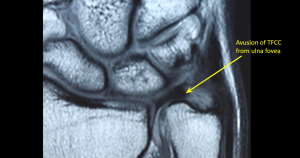

- Manyetik Rezonans Görüntüleme (MRI): TFCC yırtıklarının detaylı olarak görüntülenmesini sağlar.

- Artroskopi: Direkt olarak eklemin içini incelemek için yapılan cerrahi bir işlemdir.

TEŞHİS

Ulnar Fovea Burcu.

Bu test muhtemelen TFCC yaralanmaları için en hassas ve spesifik testtir. Hasta cerrahın karşısında otururken ve dirseği masaya yerleştirilerek, el dik olacak şekilde 90 derece fleksiyonda ve bileğin ulnar yönü doğrudan cerraha bakacak şekilde gerçekleştirilir. Cerrah bir eliyle bileği sabitlerken diğer elinin başparmağının ucuyla bileğin ulnar kısmında, ulnar stiloidin hemen üzerindeki yumuşak bölgeyi iter. Bu hassassa, test pozitiftir ve TFCC’nin stiloid ve/veya foveal bağlantı bölgelerinde olası bir yaralanmaya işaret eder.